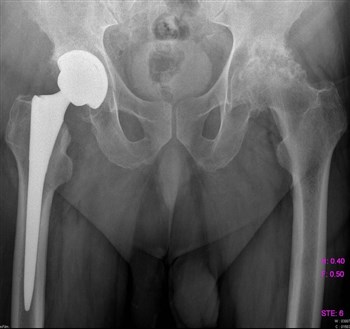

Артроз тазобедренного сустава

Из-за артроза боли в паху и пояснице чаще всего появляются у женщин в возрасте от 45 лет. Заболеванию могут подвергнуться сразу оба сустава или же один. Определить болезнь непросто, она маскируется под массу других. Первые проявления могут заключаться в том, что «ломит» около ягодиц, а боль возникает при минимальных нагрузках.

Артроз тазобедренного суставаПатология, при которой разрушаются хрящевые ткани. В запущенной стадии заболевания ограничивается подвижность в тазобедренном суставе.

Все чаще и чаще пациенты обращаются с жалобами на боли в паху, в колене, иногда на боль в ноге, на скованность движений, нарушение походки.

Как правило, страдают таким недугом женщины после 40 лет.

Боль локализуется в вышеуказанных местах как на одной, так и на обеих ногах.

Для того, чтобы поставить верный диагноз, проводят диагностику, которая включает:

1. МРТ;

2. Рентгенографию;

3. Компьютерную томографию.

Проведенная диагностика покажет, в какой стадии находится заболевание, будет дана точная информация о состоянии мягких и костных тканей.

Если заболевание не в хронической форме, или, проще говоря, не запущено, то лечение происходит обычным парацетамолом, без какого-либо хирургического вмешательства. Лечащий доктор назначает курс массажа, лечебной гимнастики, постоянный контроль ортопеда. При ноющих болях прописывается курс болеутоляющих – Кеторол, Диклофенак.

Немаловажное значение имеет обувь. Она должна быть качественной, лучше ортопедической.